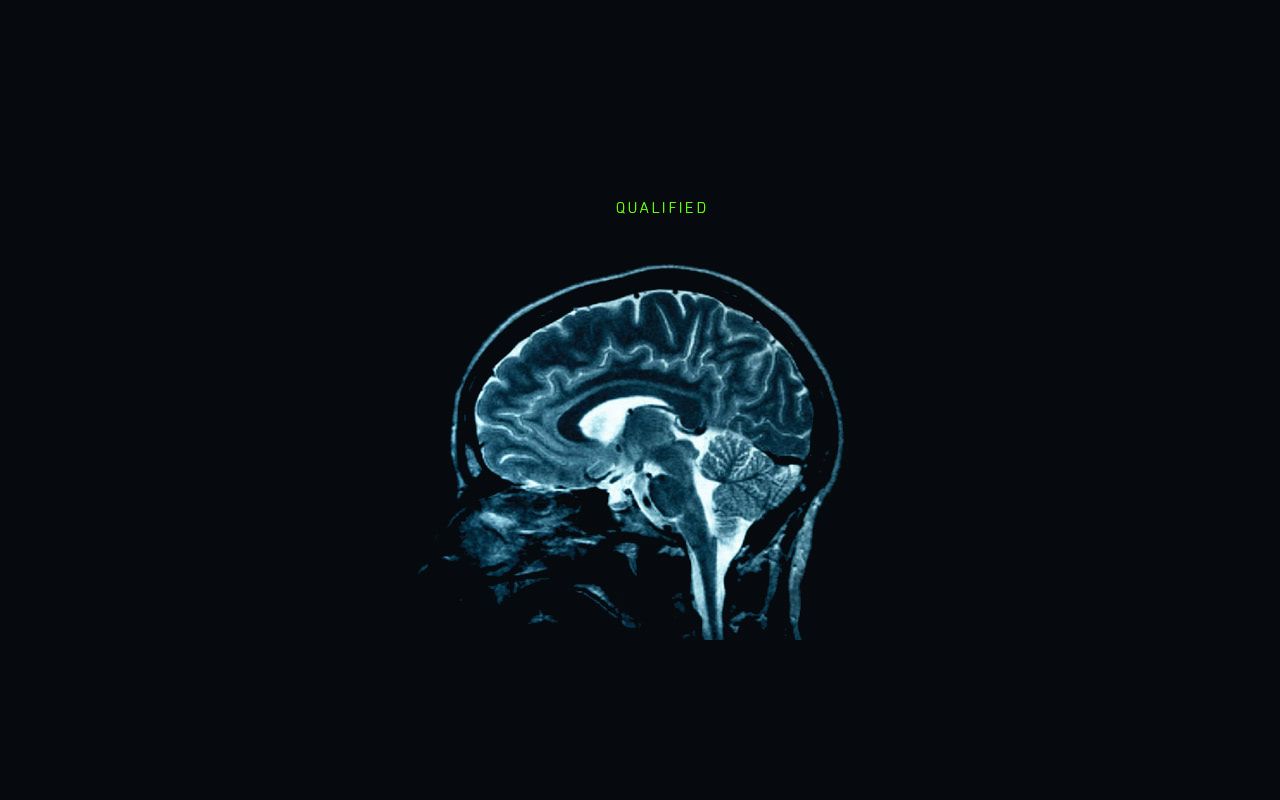

Brain Scan Replaces Job Interview in 5 Years?

Forget about palmistry! MRI scans for candidates in top jobs such as bank directors could soon become part of the ...